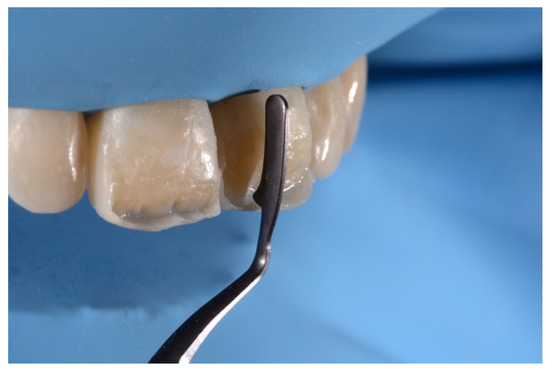

2. Case Presentation